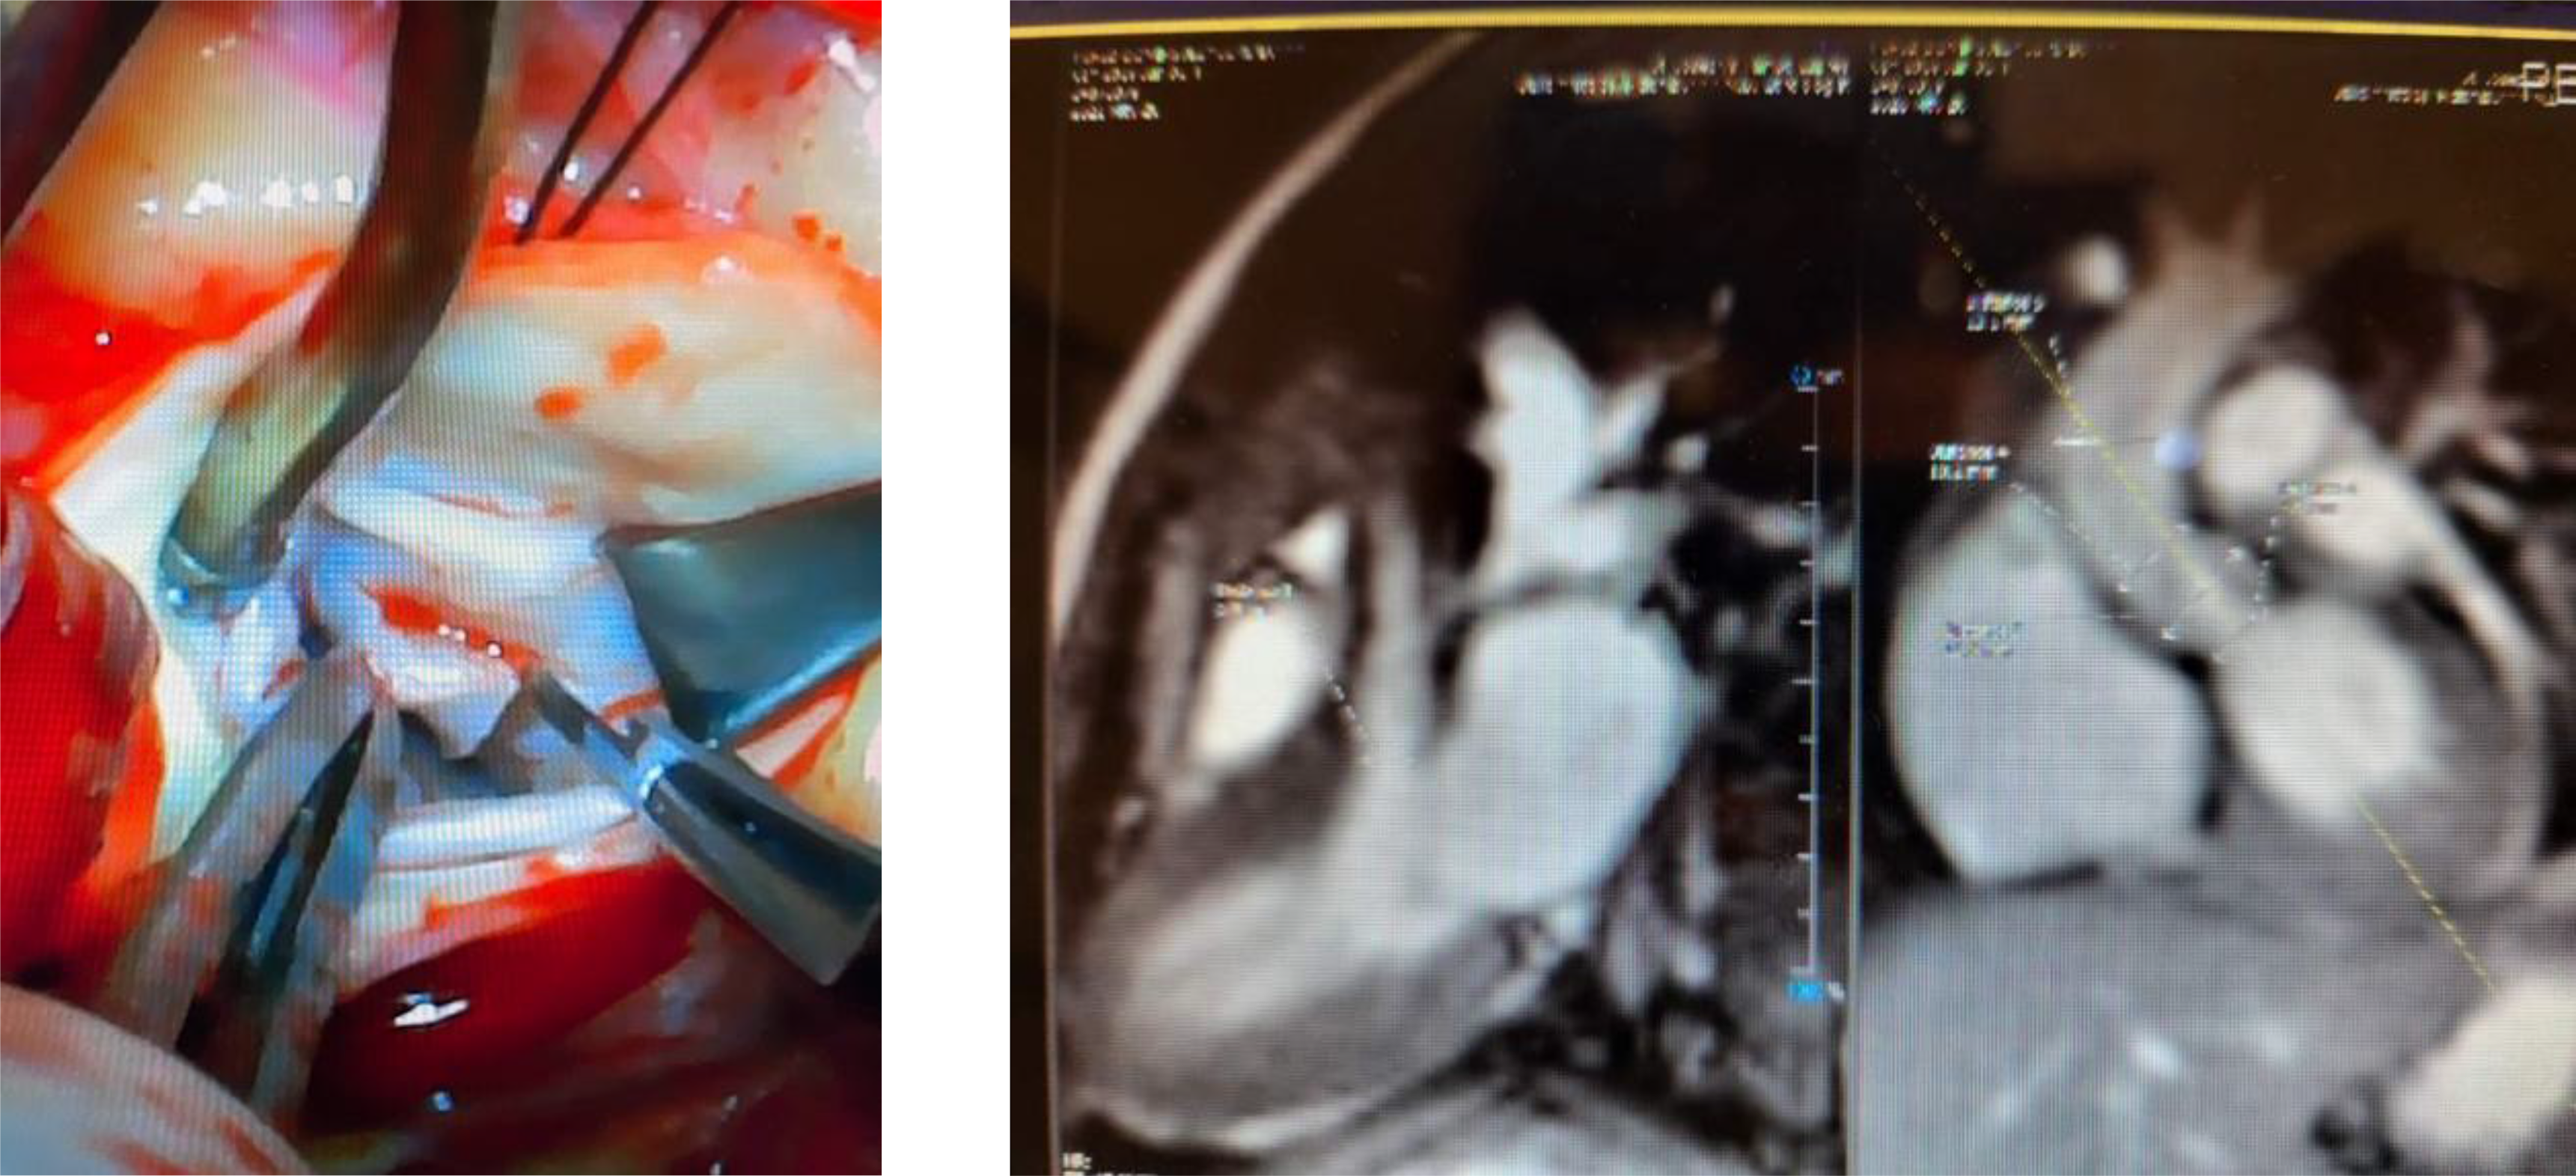

A 6-month-old female was evaluated for a heart murmur in January 2020. Echocardiogram at the initial visit was normal, hence the patient was discharged from further follow-up. She was referred due to persistent murmur at 1 year of age. Repeat echocardiogram showed a subaortic ridge with mild stenosis. Follow-up echocardiogram at 18 months of age showed a distinct oblong echogenic mass measuring 1.5 cm in the left ventricular tract. The tumour was attached to the base of the septum. Mild-to-moderate sub aortic stenosis along with mild aortic insufficiency noted. MRI of the heart showed a cardiac mass along the septal wall in the left ventricular outflow tract measuring approximately 1.7 cm, extending to the aortic valve annulus. This would be most consistent with a fibroma. This cardiac mass resulted in the narrowing of the left ventricular outflow tract to approximately 6 mm, creating outflow tract obstruction. Surgical resection of the tumour was performed in June 2021. During surgery, the tumour tissue was noted to be smooth, glistening, and pliable to nodular and indurated. The resected tumour showed an aggregate of multiple, variegated tissues that measured from 0.6 cm to 0.8 cm. Histopathology confirmed nodular fasciitis. This is shown below.